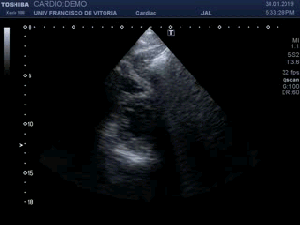

142. Ecocardiografía.Plano Apical 4 cámaras